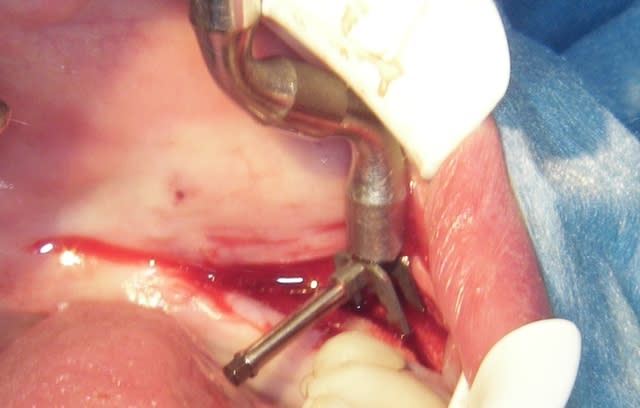

quelques photos en "grand"

--

Pour la question gestion des tissus mous, n'étant pas un "pro" de la gencive, je dirais que dans tous les cas j'incise au minimum, j'ai toujours pratiqué ainsi, même à l'époque ou les tendances étaient d'inciser large.

J’ai toujours eu l'impression que moins on décolle moins on n'a de problèmes.

Pour l'élévation mandibulaire, je ne cherche pas 5cm mais 5 à 8 mm donc je préfère ne pas toucher au coté lingual.

L’utilisation du piézo permet de couper seulement l'os, et la muqueuse garde son action.

Je ne sais pas pourquoi ton conférencier avait besoin d'une incision sous le mylo, en général je n'y vais pas

Mettre de la simplicité dans les techniques "compliquées" ça ne mange pas de pain.